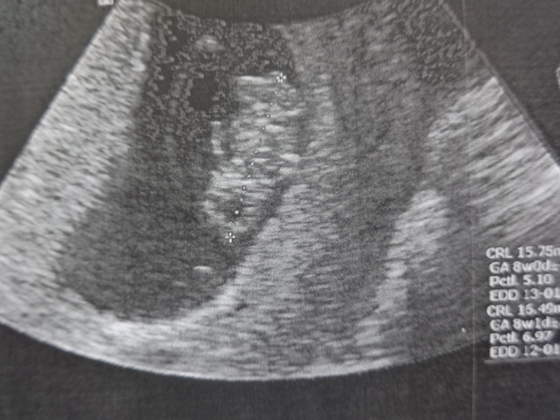

ALe Fasol jest super, śliczny, równo o 2 tygodnie urósł, czyli jak powinien. Wyniki badań też w porządku i ogólnie dobrze. Kolejna wizyta 23 czerwca i już na NFZ, uff odciąży to trochę mój portfel

A to mój Fasolek, wymiary chyba widać na zdjęciach